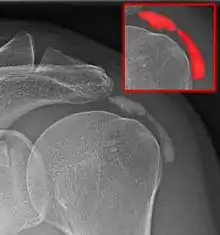

Calcific bursitis refers to calcium deposits within the bursae. This most occurs in the shoulder area. The most common bursa for calcific bursitis to occur is the subacromial bursa. A bursa is a small, fluid-filled sac that reduces friction, and facilitates movements between its adjacent tissues (i.e., between tendon and bone, two muscles or skin and bone). Inflammation of the bursae is called bursitis.